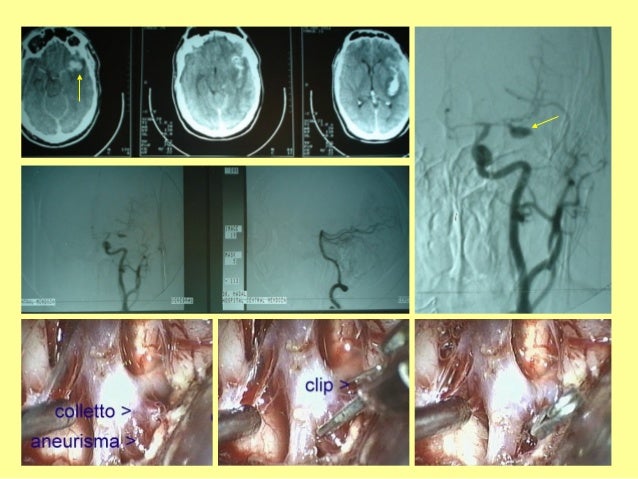

28. 28. HIPE HEMORRAGIAINTRAVENTR.ANGIOPATIAAMILOIDEA.